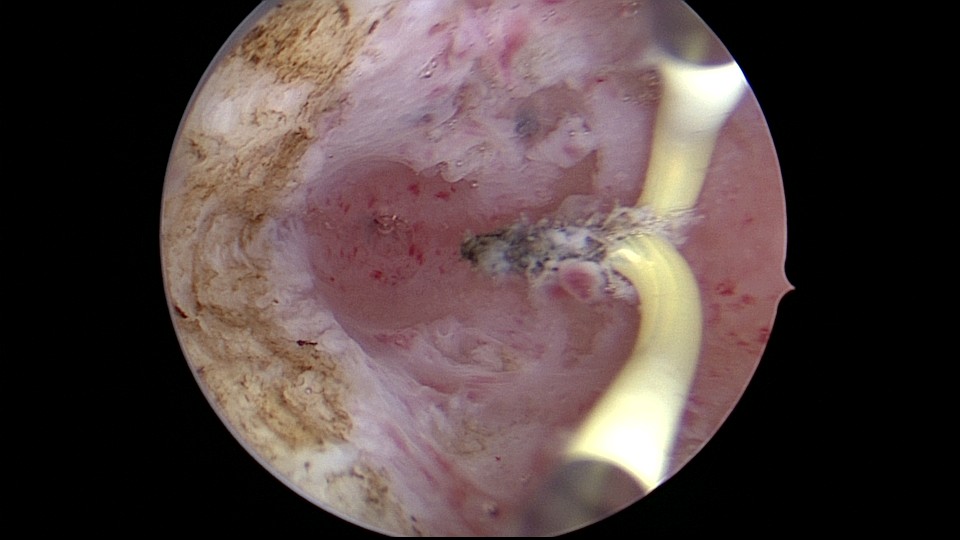

患者35岁,G5P0,继发不孕10年,10年前外院开腹宫外孕手术1次,试管失败1次。外院B超提示宫腔粘连,2021年4月在成都西囡妇科医院做宫腔镜检查,发现宫腔粘连。2021年11月到我院做宫腔镜分粘手术,术中见宫腔两侧及右侧宫角致密粘连,内膜片状充血,单极电切分粘,恢复宫腔形态,显露双侧输卵管开口。2021年12月宫腔镜二探取球囊,宫腔形态正常,双侧输卵管开口可见。分粘后再次试管成功,足月分娩。现40岁,G6P1。